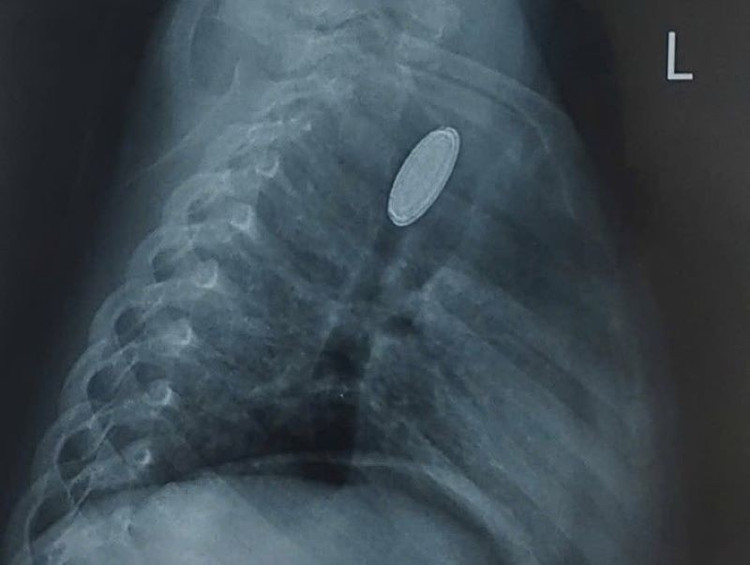

Đồng xu rơi vào thực quản bệnh nhi và được gắp ra - Ảnh BVCC